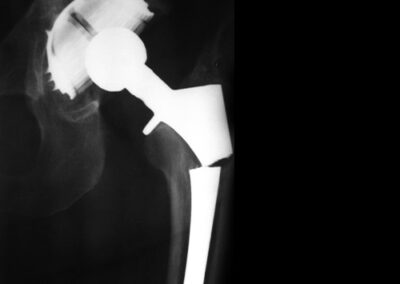

- Luxação: pode ocorrer em até 3% nas artroplastias primárias e em até 10% nas revisões. A luxação ocorre mais comumente até seis semanas da cirurgia, mas pode ocorrer muitos anos após o procedimento cirúrgico, acompanhadas por soltura dos componentes. Pacientes que apresentam luxações traumáticas agudas tem melhor resposta à redução e imobilização Fig. 16.

Fig. 16. Exemplos de luxação de prótese total de quadril pelos mais diversos motivos.